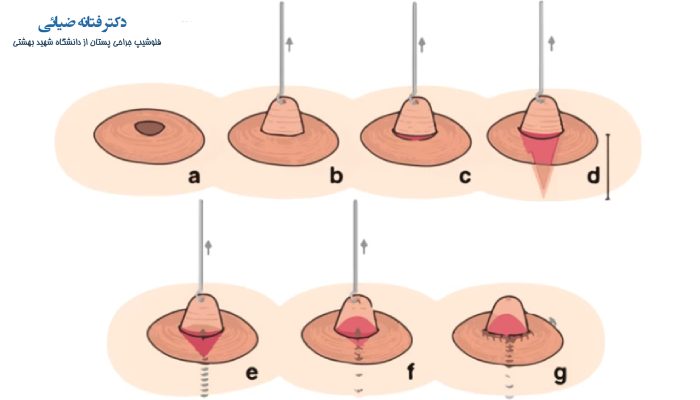

3. جراحی بیرون کشیدن نوک سینه

در مواردی که میزان فرورفتگی نوک سینه شدید باشد و هیچ کدام از راه های قبلی پاسخ گو نباشد، به تشخیص پزشک باید جراحی انجام شود. این جراحی که به صورت سرپایی انجام می شود با ایجاد برش هایی و کنار زدن پوست هاله سینه و ایجاد تغییراتی در مجاری شیری، نوک سینه بیرون آورده می شود.

در این جراحی میزان ظرافت و دقت در حین انجام جراحی بسیار مهم است تا نگرانی از جهت باقی ماندن زخم و اسکار در پوست سینه وجود نداشته باشد؛ در نتیجه حتما باید برای انجام چنین جراحی به بهترین دکتر سرطان سینه مراجعه شود.